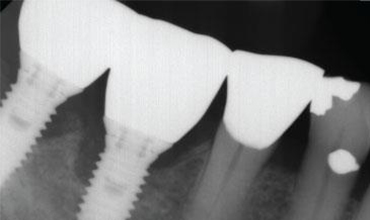

Implant complications have become a major challenge for many dentists who placed implants. This lecture is designed to help dentists who placed or restored implant understand what’s new in this field and how to avoid these problems. New definitions such as plaque induced peri-implantitis and non-plaque associated peri-implant diseases as well as treatment prognosis of peri-implant diseases will be presented. Recent research findings of how surface coating or the titanium particles influence the incidence of implant complications will be discussed. In addition, this lecture will provide the mechanisms (e.g., surgically triggered, prosthetically triggered and biological induced implant complications) of how implant bone loss and implant failure occurred. Specifically, how to manage implant esthetic, biological, biomechanical complications will be demonstrated. Three decision trees (implant biological complication management, implant treatment based upon defect morphology and implant soft tissue recession classification and proposed management) will be proposed. The treatments for implant diseases/complications include: chemotherapeutic agents, lasers de-contamination, apically positioned flap with or without implantoplasty, implant surface detoxification, lasers, guided bone regeneration, soft tissue grafts, implant removal as well as re-implantation will be thoroughly discussed.